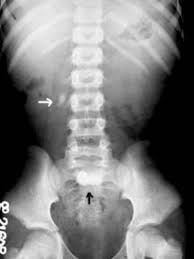

There was no significant difference in measured size between kub and ct p 0 11. Do all kidney stones show up on a kub kidney xray. Combining ultrasound with a kub while not as sensitive or specific as a ct scan does do a pretty good job of picking up clinically significant stones.

A counter argument for using ultrasound in diagnosing of kidney stones is that ureteral stones are usually difficult to visualize with ultrasound and unless they are located at upj or in the distal ureter will not be seen with ultrasound.

Patients with serum creatinine 1 8 mg dl were. The other common study for kidney stones are plain x rays of the abdomen known as kub s which stands for kidney ureter bladder. Patients with serum creatinine 1 8 mg dl were. We then compared accuracy of stone measurement from kub with ct.